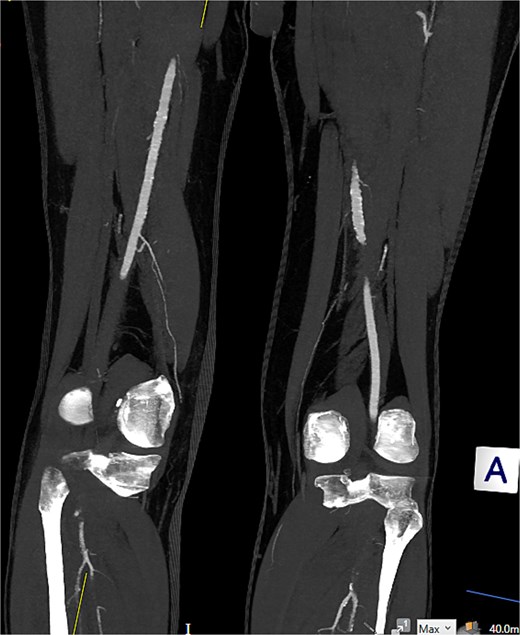

Computed tomography (CT) angiography (Figs 1 and 2) revealed a near-occlusive filling defect at the left common iliac bifurcation. Further embolic material extended into the left common femoral bifurcation, profunda femoris, and superficial femoral artery. An embolic occlusion was also present in the below-knee popliteal artery, extending to the trifurcation, with partial reconstitution of the calf vessels. Emboli were seen in the posterior tibial and peroneal arteries. On the right side, embolic material was noted in the distal profunda and popliteal artery, with further emboli in the tibio-peroneal trunk. The patient underwent bilateral femoral thromboembolectomy.

A near-occlusive filling defect at the left common iliac bifurcation. Further embolic material extended into the left common femoral bifurcation, profunda femoris, and superficial femoral artery.

Embolic occlusion of the below-knee popliteal artery extending to the trifurcation, with partial reconstitution of the calf vessels. Emboli are also present in the posterior tibial and peroneal arteries.